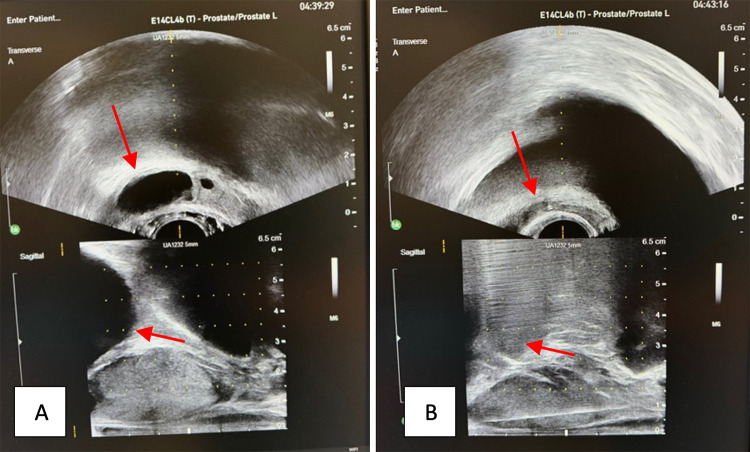

A 44-year-old healthy Caucasian gentleman presented with fevers and right lower quadrant pain. He had mildly elevated inflammatory markers and computed tomography demonstrated cystic enlargement of the right seminal vesicle concerning for seminal vesicle abscess (SVA). SVA is a rare diagnosis and generally requires drainage for adequate source control. The patient was commenced on intravenous antibiotics and underwent uncomplicated transperineal drainage of seminal vesicle abscess under local anaesthetic. Urine culture confirmed infection with Citrobacter koseri and the patient was discharged on the first post-operative day with a 14-day course of oral co-trimoxazole. Six-week follow-up with multiparametric magnetic resonance imaging of the prostate shows no evidence of any prostatic lesions, prostatitis or recurrence of abscess.